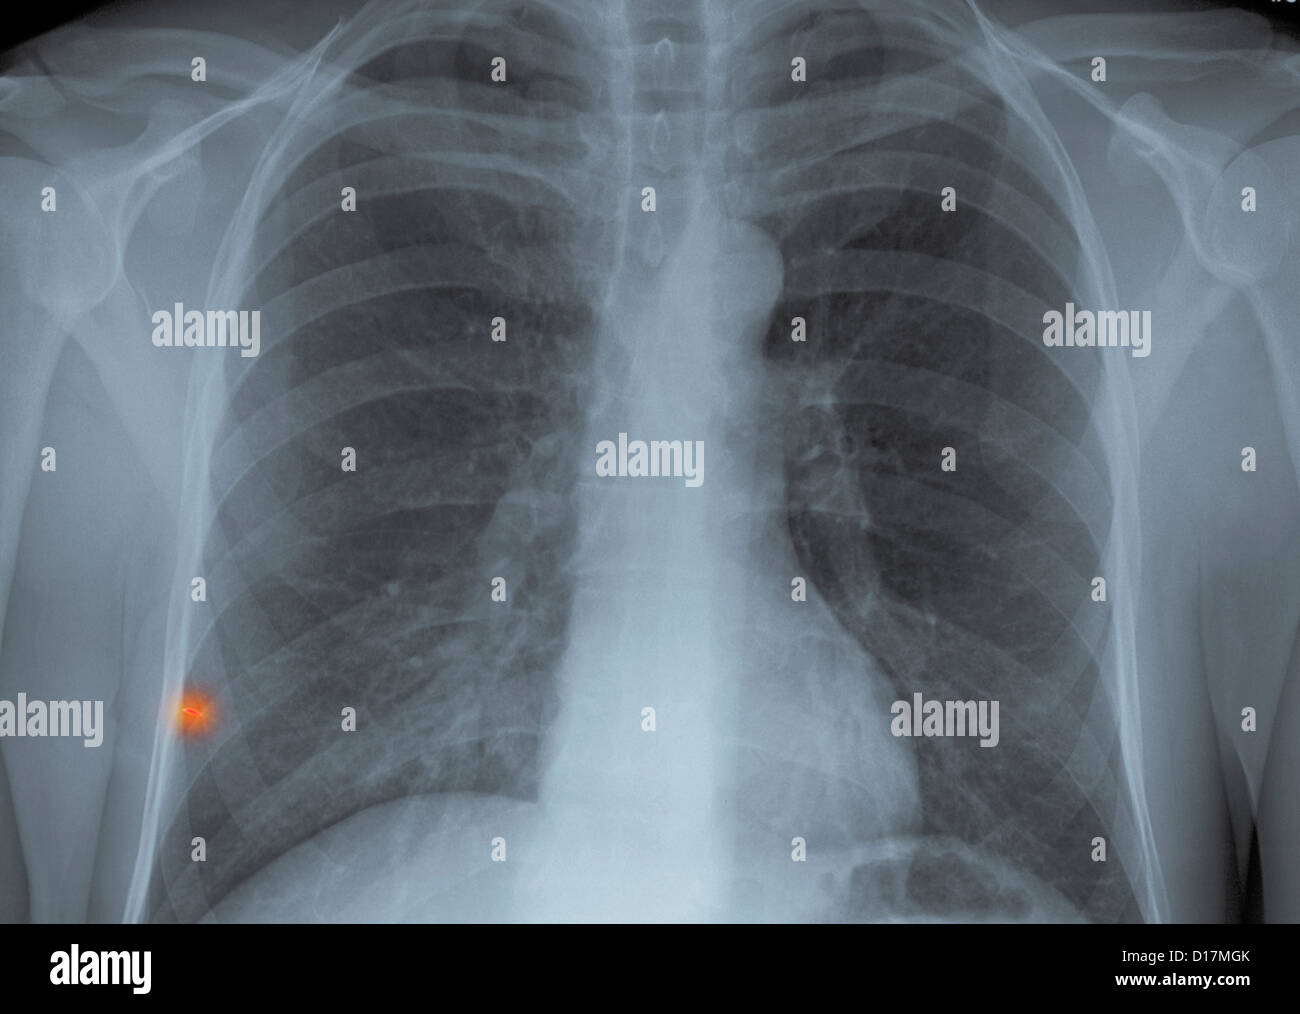

Chest Xray metal foreign body in lung Stock Photo Alamy Chest X-Ray For Foreign Body Lower airway obstruction necessitates a good history and physical especially in children and developmentally delayed individuals, and. The expectation is that the dependant lung will. The chest radiograph shows a radiopaque material (arrow) in the rbi. The coronal multiplanar reformation images. The radiological appearance in plain radiography of foreign bodies depends on three factors: On the basis of the location. Chest X-Ray For Foreign Body.

Chest X-Ray For Foreign Body . On the basis of the location of a foreign object in the body determined by a preceding clinical evaluation, frontal and lateral radiographs of the neck, chest, or abdomen can be obtained. The expectation is that the dependant lung will. The chest radiograph shows a radiopaque material (arrow) in the rbi. When foreign body aspiration is suspected, screening radiographic studies include anteroposterior (ap) and lateral imaging of the soft tissues of the neck, inspiratory and expiratory. We aim to determine the utility of ct scan as a method to accurately confirm pediatric airway foreign bodies (afbs), the current gold. The radiological appearance in plain radiography of foreign bodies depends on three factors: Lower airway obstruction necessitates a good history and physical especially in children and developmentally delayed individuals, and. The coronal multiplanar reformation images.